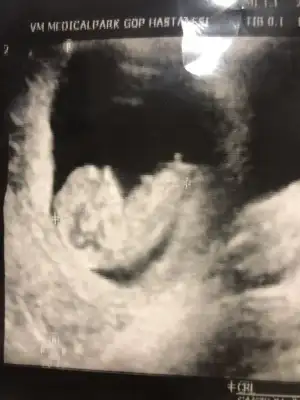

Ikra meyra Ikra meyra canım 13 haftalık videosundan resimler çektim. Ben çıkıncı görüyorum sen görüyormusun Screenshot_20210123-083957_Video Player.webp Screenshot_20210123-084338_Video Player.webp Screenshot_20210123-083911_Video Player.webp Screenshot_20210123-083543_Video Player.webp